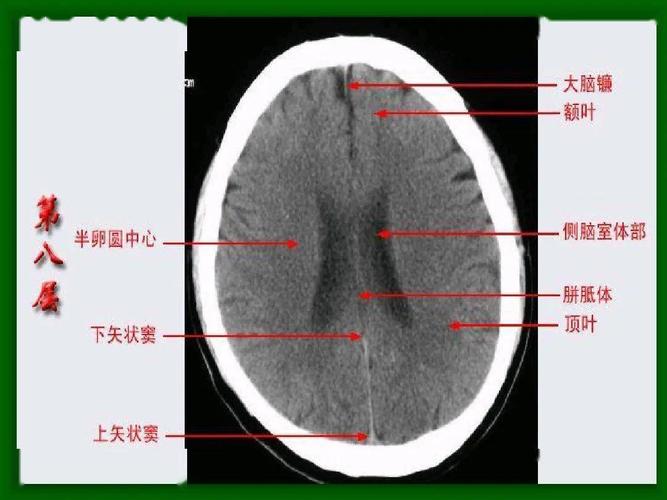

头颅ct 解剖图谱,人手一份

正常头颅ct图片

头颅ct图片

正常头颅ct